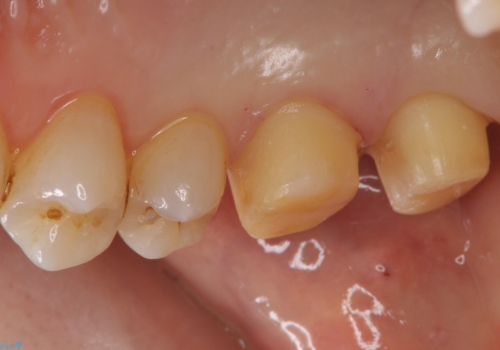

銀の詰め物を除去した後、その奥にある古い詰め物も除去し完全にむし歯を取り切ったことを確認してからセラミッククラウンを装着していきます。

詰め物の除去後、残った歯が薄い場合は今後の破折リスクを考慮して被せ物での修復処置を提案することがあります。